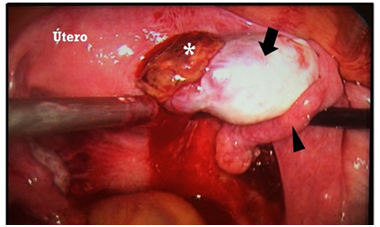

Female patient of 30 years of age, married, menarche at 10 years of age, 30x4 rhythm, with a history of dysmenorrhea, G1, P0, A0, C0. She went to a gynecologist-obstetrician for pregnancy control (7.5 SDG), referring to occasional colic and brown transvaginal waste without other aggregates. Within the analyzes of laboratory is found with Hb 12.5g / dl, leukocytes 8,000 uI, glucose 96mg / dL, β-HCG 2551mUI / mL, as well as general urinalysis (EGO) without alterations. On examination, transvaginal touch was performed, finding whitish leucorrhoea not fetid, so pelvic ultrasound (transabdominal) was requested, and qualitative control of β-HCG, and it was mentioned two days later. In this ultrasound uterus is reported without evidence of gestational sac (Figure 1) and second quantification of β-HCG of 2688mUI/mL. It is mentioned for the third time two days after showing ascending β-HCG quantification (2708mIU/mL), so it was decided to perform a new sonographic study by transvaginal route, confirming the presence of an empty uterine cavity (Figure 2); In addition, right ovary is observed with two nodules adjacent and inseparable from it; one of them with a hypoechoic aspect of 3 cm in diameter and the other of ecogenic appearance of 2.8 cm in diameter (Figure 3); later they are explored with Doppler mode, observing peripheral vascularity in the first (ring of fire sign) and scarce internal vascularity in the second considering itself what may correspond with body lute Y coat gestational disorganized respectively. Finally, indirect compression maneuvers are performed through the transducer, drawing attention to the "block" mobility of the right ovary with these nodules, which is why the probability of ectopic ovarian pregnancy is highly considered (Figure 4). It is sent with a treating doctor who decides to perform surgery (Figure 5); tissue samples are sent to study pathological he which reports "Findings compatible with pregnancy ectopic ovarian " (Figure 6).

Figure 5 Photograph taken during the surgical procedure in which the body of the uterus, ovary (fleche), salpinge (point of fleche) and suspicious nodule (*) inseparable from the annex are observed.